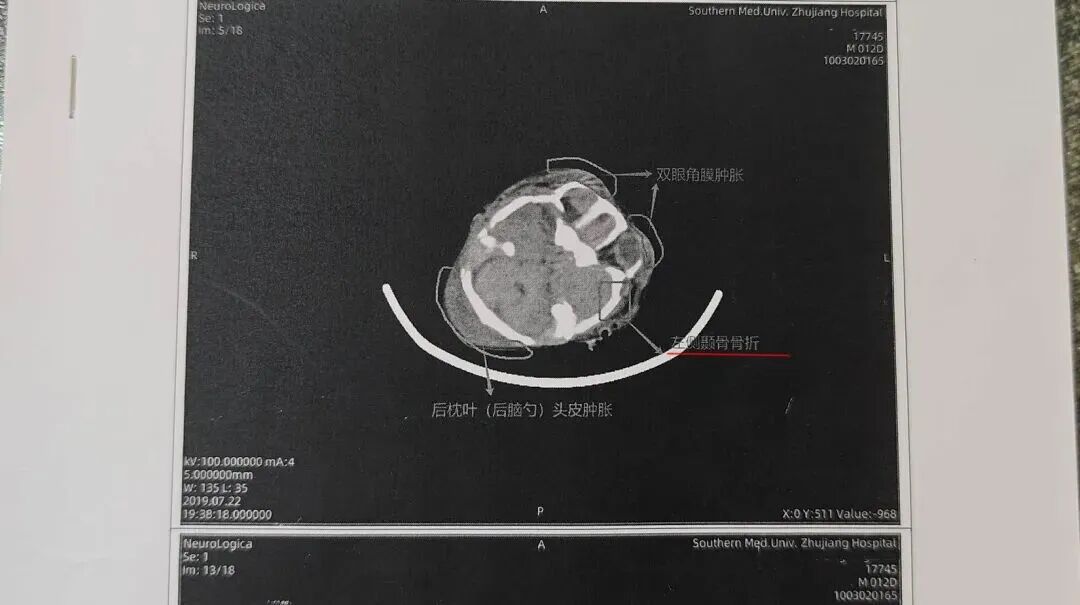

•2019年7月22日(出生第12天):CT显示双侧顶枕部软组织肿胀,医师判断为硬膜下及蛛网膜下腔积血、髓鞘发育未完全。

2026年3月6日,《远程影像咨询意见书》出炉,明确诊断:孩子左侧颞骨、右侧颞骨、枕骨均骨折,矢状缝分离,伴随多处脑出血、头皮血肿。

北京一脉阳光影像中心在《远程影像咨询意见书》中指出患者有多处颅骨骨折